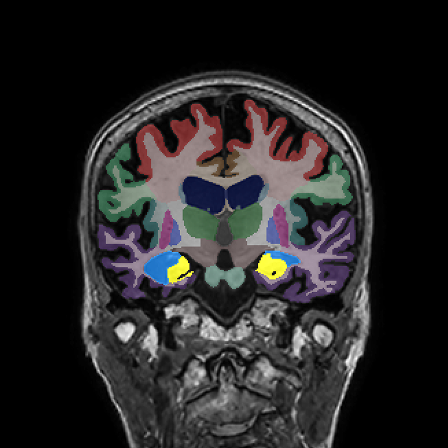

Longitudinal Tracking

Alzheimer's Disease Case Study 2

Retrospective brain volumetric analysis in a female patient diagnosed with Alzheimer’s disease at age 77 showed progressive brain atrophy over a 5-year period. The scans demonstrate temporal cortical atrophy with marked ex-vacuo enlargement of the lateral ventricles.

PATIENT

Female patient diagnosed with Alzheimer's Disease at Age 77

Analysis period

5 years

regions of interest

Temporal cortex

Hippocampus

Inferior lateral ventricles

Age 72

Age 74

Age 77

Lateral ventricle